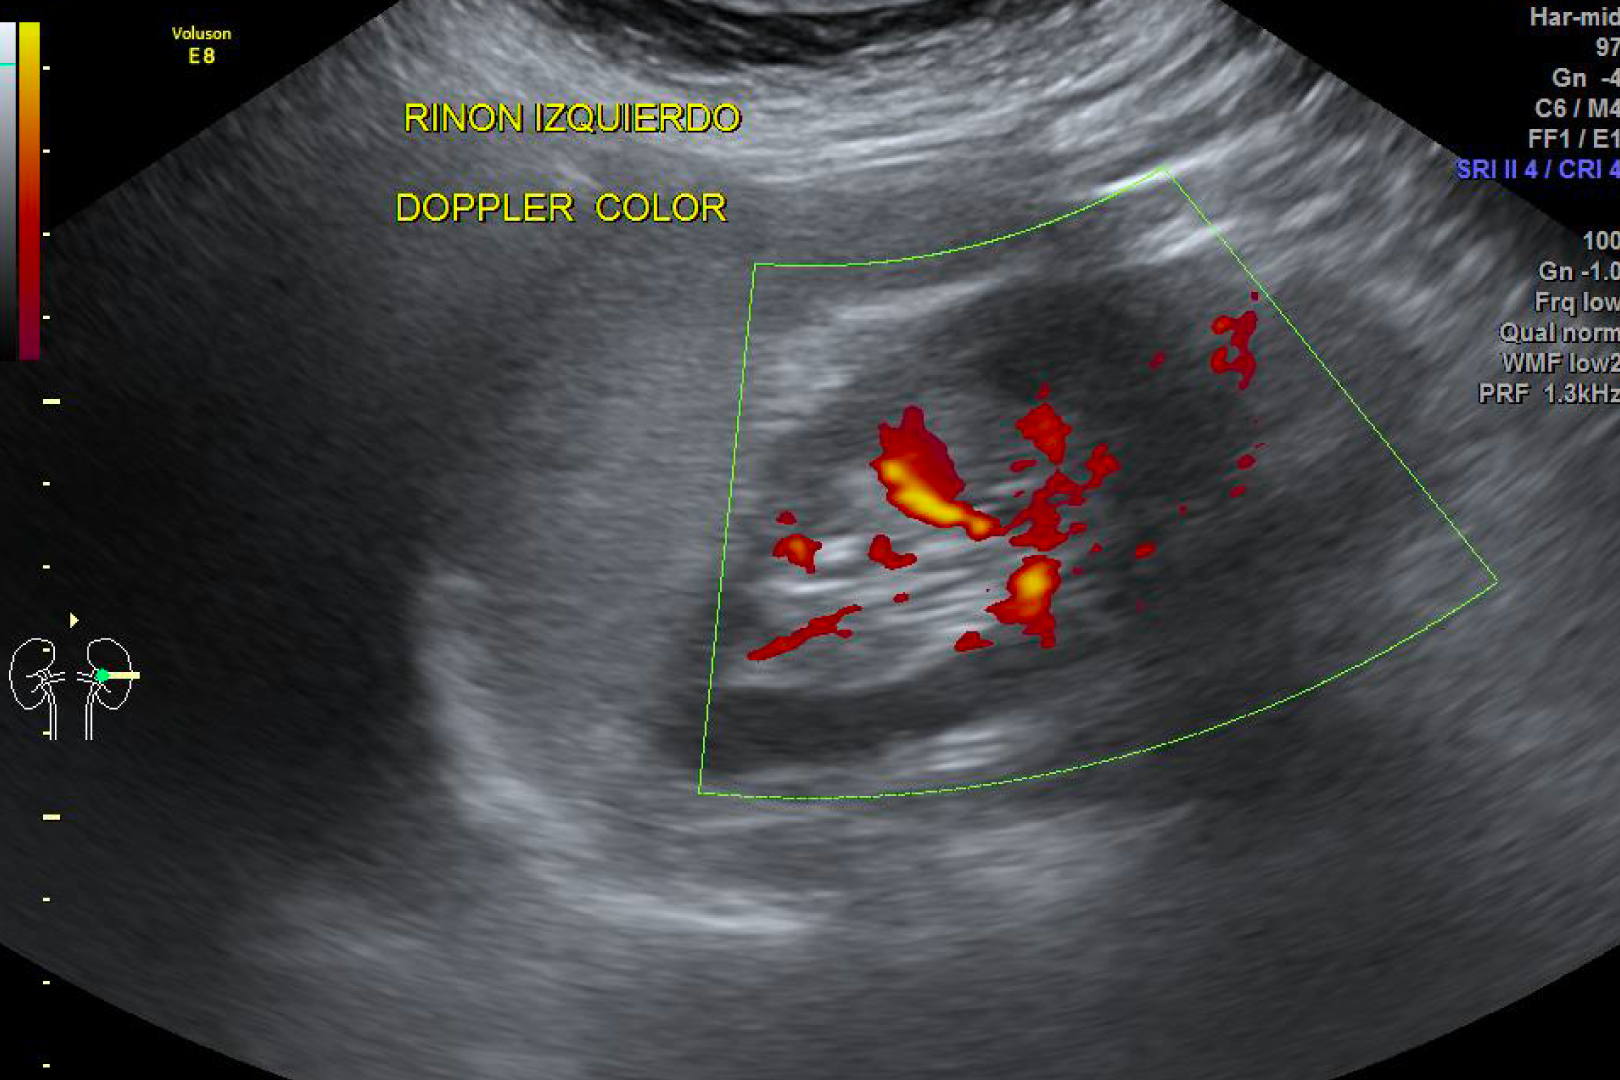

HD Live quinta dimensión, Imágenes de volumen con profundidad y claridad, que aportan un realismo anatómico para un mejor diagnóstico.